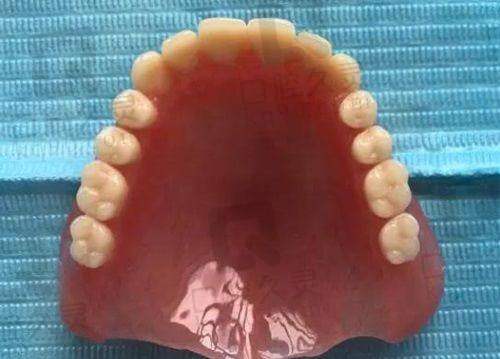

专精的医生团队是关键。南宁岭南口腔门诊部拥有一支专精且经验多的医生团队。这些医生大多毕业于有名的口腔医学校校,具备扎实的理论基础。他们在口腔领域深耕多年,有着丰富的临床经验。比如在牙齿矫正方面,医生们能够根据患者的不同牙齿情况,制定个性化的矫正方案。无论是传统的金属牙套矫正,还是隐形矫正,都能精细操作,确保矫正成效。许多患者反馈,在该门诊部接受牙齿矫正后,牙齿排列变得整齐美观,咬合关系也得到了明显改善。